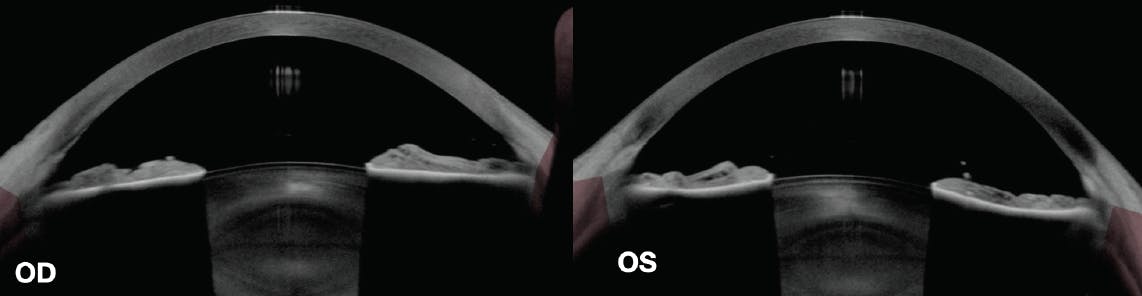

On examination, unmedicated IOP was 19 mm Hg OU. The optic nerve in the right eye looked relatively healthy, whereas superior thinning was clearly evident in the left eye (Figure 1). Visual field progression was confirmed in the left eye (Figure 2), and progressive damage to the retinal nerve fiber layer of each eye was observed, although the findings were more subtle in the right eye (Figure 3). A laser peripheral iridotomy (LPI) had been performed on the right eye in 2010 and was found to be patent. Visual fields from 2010 were available (Figure 4). Anterior segment imaging confirmed the presence of posterior bowing of the iris in the left eye but not the right eye (Figure 5).

Figure 5. Anterior segment OCT (AS-OCT) imaging of the right eye (at left) shows a flat iris profile after LPI. AS-OCT imaging of the left eye (at right) shows posterior bowing of the iris in the absence of an LPI.